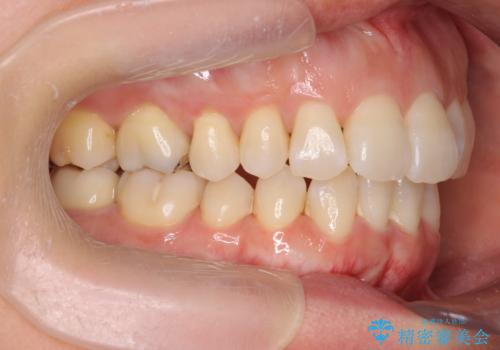

職業柄ワイヤー矯正ができない、マウスピース矯正で行う八重歯抜歯症例

- 「長年気になっている八重歯を矯正治療で治したい、ただし職業柄ワイヤー矯正は絶対にできないのでマウスピース矯正を希望。」

、と矯正治療を希望され来院されました。

通常は八重歯の抜去は行わず、小臼歯の抜去を行いワイヤー矯正を行いますが、八重歯を抜去することでマウスピースで現実的に達成できる機能的な歯並びを獲得できるよう治療計画を立案します。

治療に制約がある場合でも、現実的な治療ゴールを設定することで機能的・審美的な歯並びを手に入れることができました。